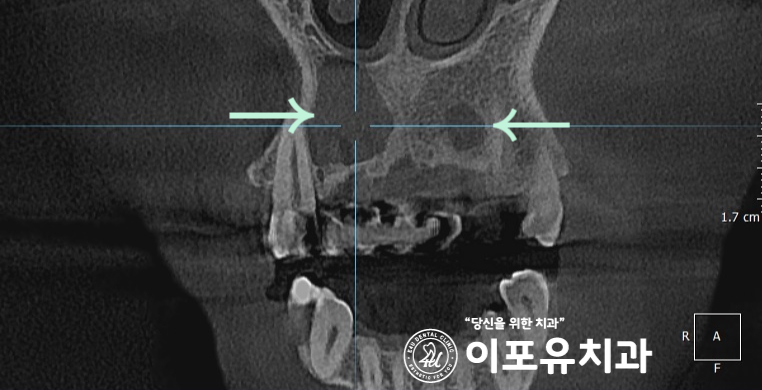

CT를 촬영하여 살펴보면

생각보다 큰 크기의 병소가 관찰됩니다.

아무래도 쉽지 않은 케이스로 보입니다.